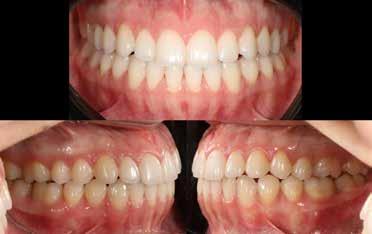

A vegyes fogazati kezelési célok a fogívek tágítása és a mandibula meziális irányú növekedésének a biztosítása volt. Fontos, hogy az ilyen típusú készülékeket nem csak éjszaka, hanem napközben is – amennyit csak lehet – hordani kell a minél hatékonyabb működés érdekében. A 18 hónapos első fázisú kezelésnek köszönhetően az alap kezelési célok megvalósultak, sikerült a class 1-es okklúziót beállítani (4-7. képek).

terséges harapásemelés pedig az alsó hatosokra, majd később a felső négyesekre került (8. kép). Az intermaxilláris elasztikus gumihúzás class-2-ess vektorú volt annak érdekében, hogy a disztálharapás korrekciója tökéletes legyen (9. kép). A harapást beállító elasztikus gumihúzásokat – mint minden kezelésnél –, ebben az esetben is folyamatosan, az egész kezelés alatt 24 órában (étkezések kivételével) viselte páciensünk.

A második Pitts-21 fix készülékes fázis ideje 16 hónap volt (10-12. képek)